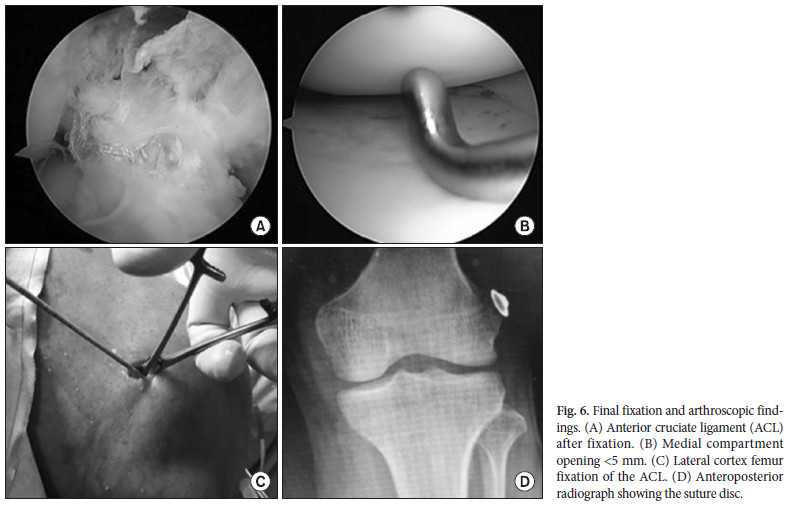

Pour la fixation finale, une incision a été faite sur la face latérale du fémur et les deux extrémités du FiberTape ont été attachées sur le disque de suture (Fig. 6C). A l’arthroscopie, le LCA était bien en position et tendu (Fig. 6A), et le compartiment médial présentait une ouverture <5 mm (Fig. 6B). A la radiographie, le disque de suture était posé sur l'os (Fig. 6D).

Pour la fixation finale, une incision a été faite sur la face latérale du fémur et les deux extrémités du FiberTape ont été attachées sur le disque de suture (Fig. 6C). A l’arthroscopie, le LCA était bien en position et tendu (Fig. 6A), et le compartiment médial présentait une ouverture <5 mm (Fig. 6B). A la radiographie, le disque de suture était posé sur l'os (Fig. 6D).